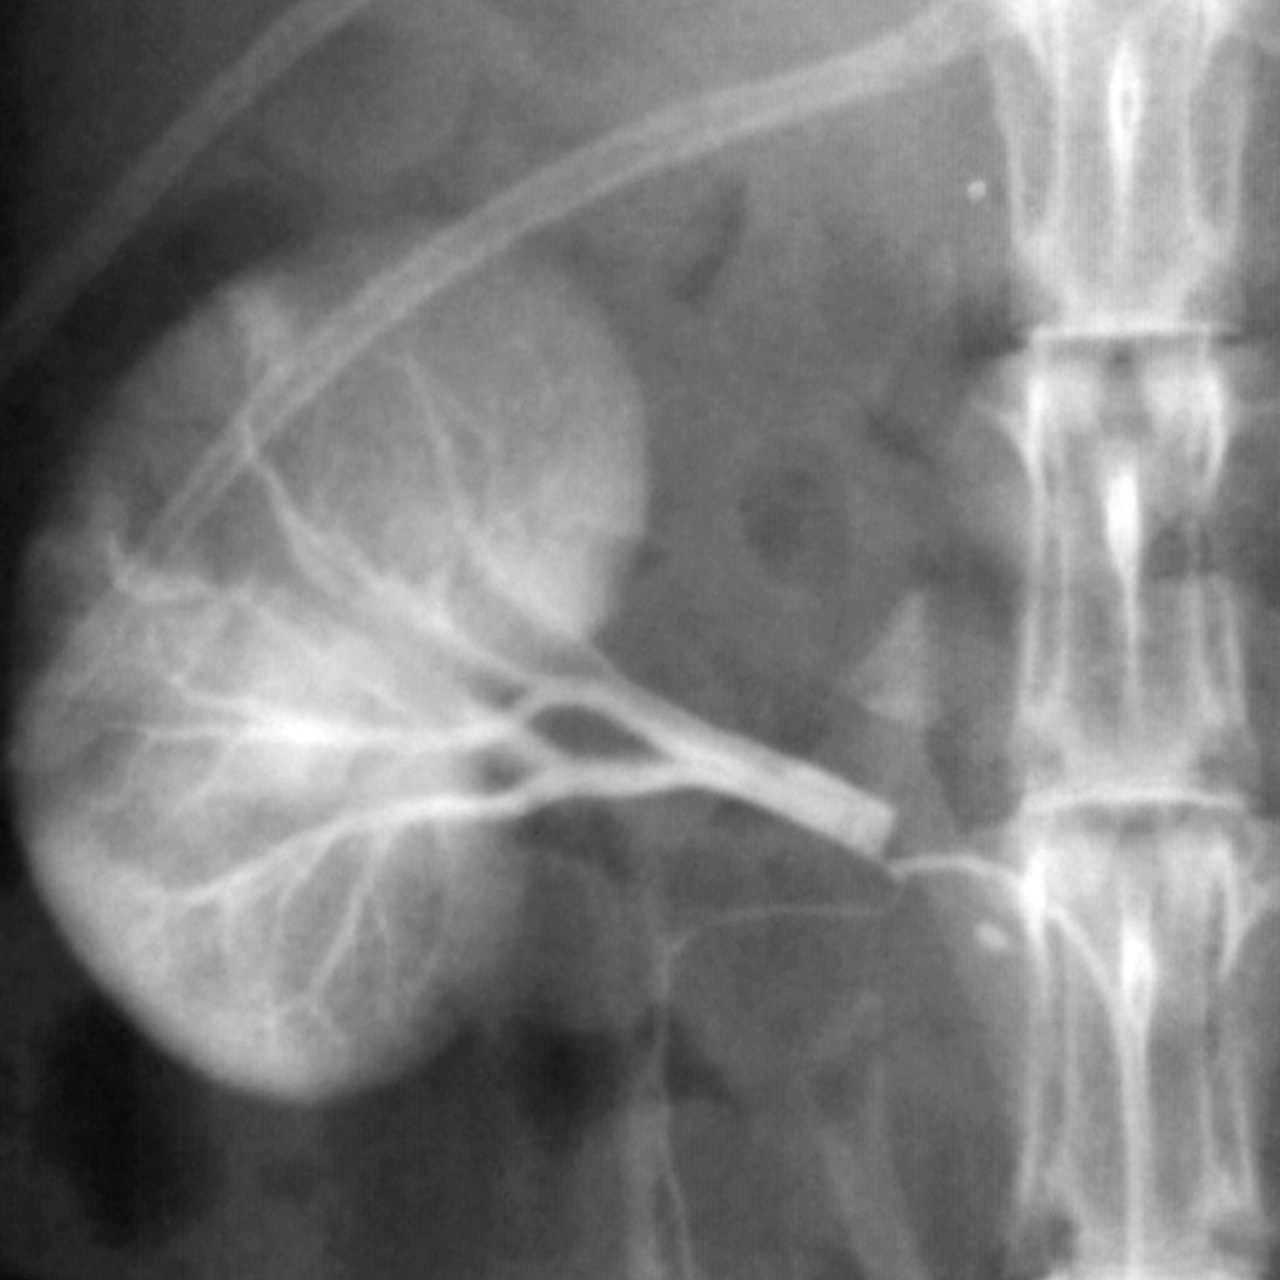

Blood pressure homeostasis is achieved by the coordinated action of several bodily systems and the kidney plays a prominent role. The renal sympathetic efferent nerves contribute to volume and BP homeostasis as they innervate the renal tubules, vasculature, and juxtaglomerular apparatus, all of which can impact BP. Historically, surgical lumbar sympathectomy was used for reduction of “resistant hypertension” before effective antihypertensive medications were available. This approach was complicated by significant side effects, such as postural hypotension, syncope, and impotence. Selective renal denervation may offer help for patients with resistant hypertension. With the emergence of interventional techniques for selective ablation of efferent nerves, enter this intriguing study.

It showed that this novel catheter-based device produced renal denervation and had a substantial decrease in BP in a select group of 45 patients with resistant hypertension.

1. Renal denervation with a 47% reduction in renal noradrenaline spillover (a marker of sympathetic efferent activity)

2. 43/45 had no adverse events. 1 patient had renal artery dissection treated with stent. 1 patient had pseudoaneurysm of the femoral artery.